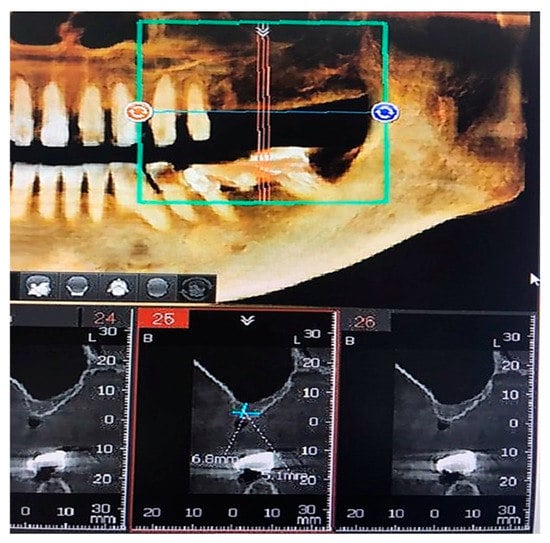

The cone-beam CT images before treatment also showed a vertical bone loss in the posterior maxillary region (Figure 7). In the jaw, the maxilla region is the most frequently experiencing vertical bone loss and the most difficult to treat [,]. Therefore, both moderate and severe bone loss in this region require a bone graft to treat it [].

Figure 7.

Cone-beam computed tomography (CT) images before treatment.